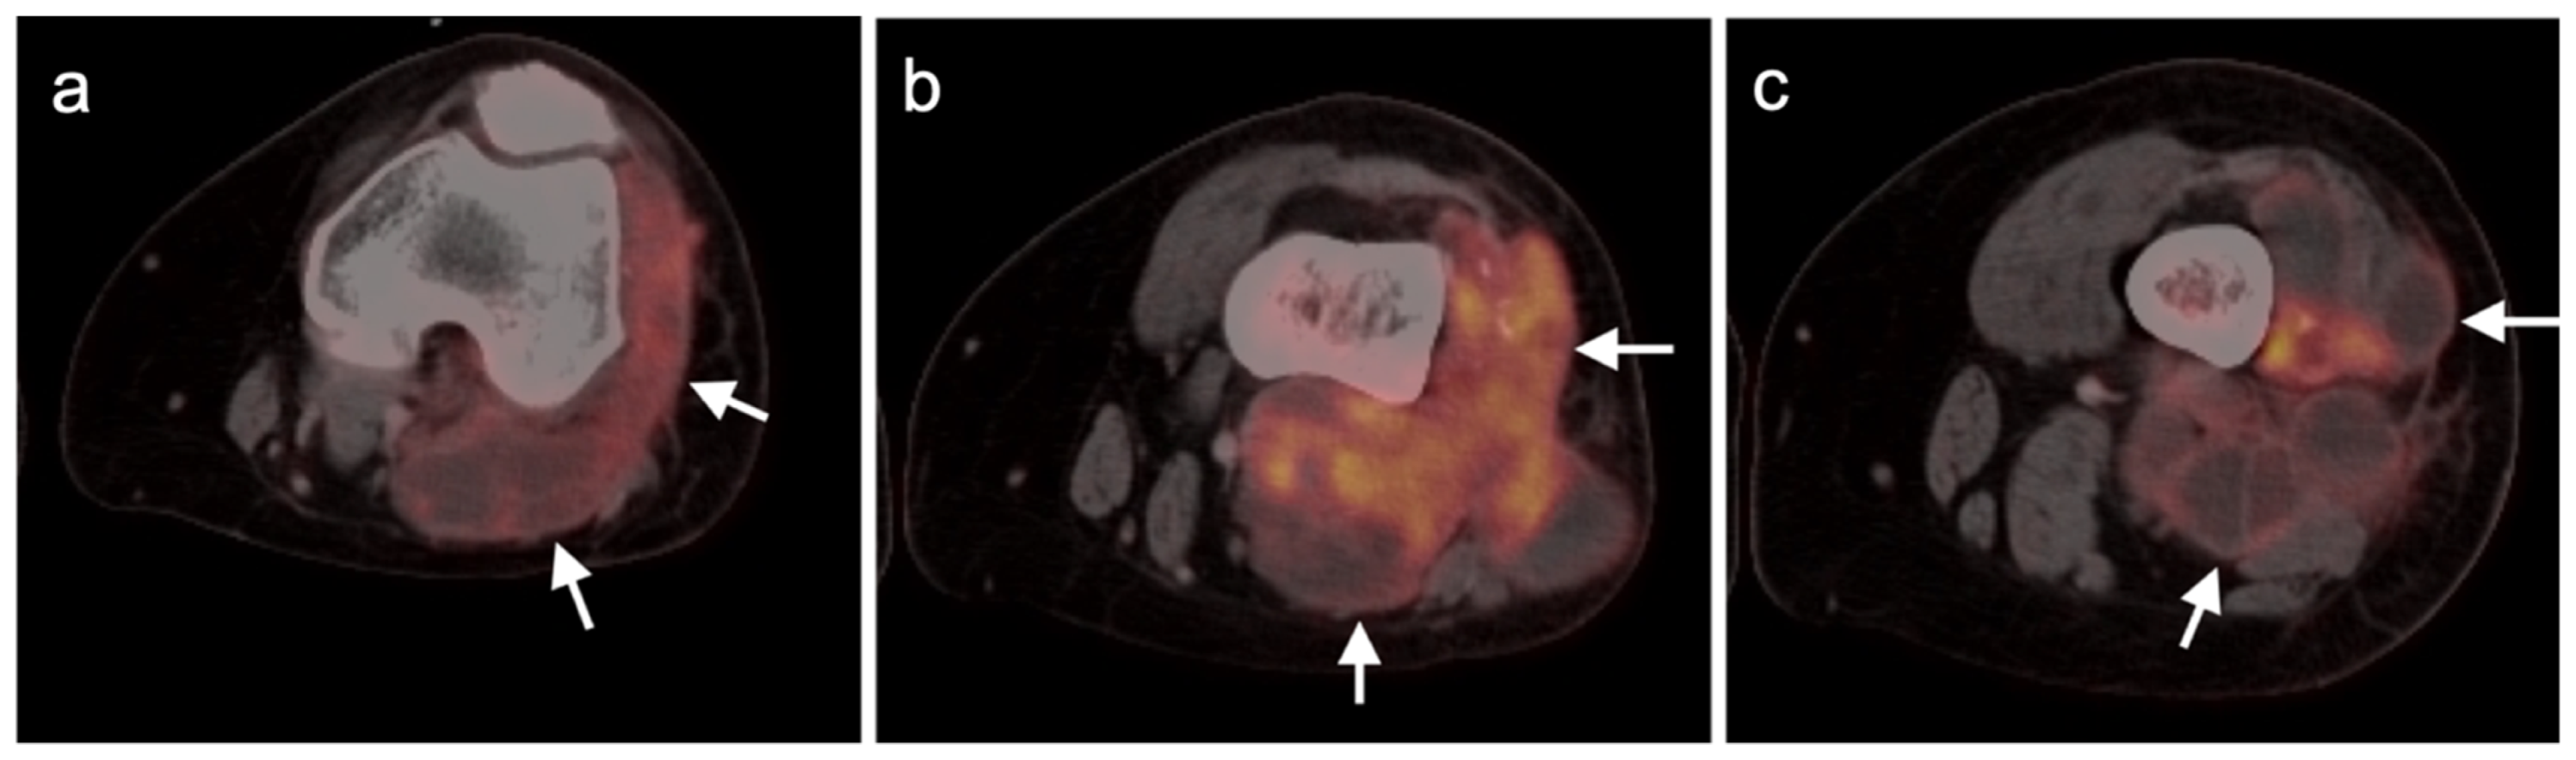

3.1. Soft Tissue Sarcomas

3.1.1. Undifferentiated Pleomorphic Sarcoma

3.1.6. Liposarcoma

3.1.7. Synovial Sarcoma